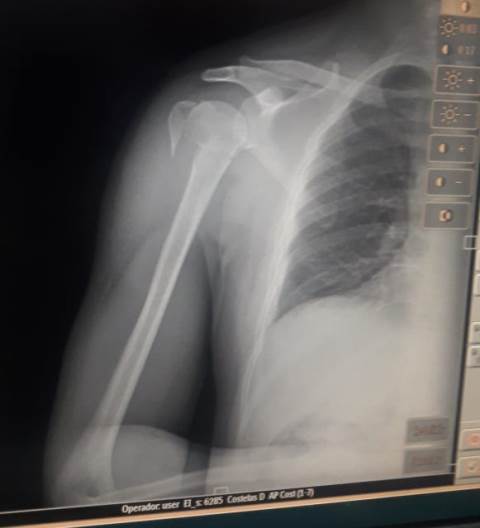

Explica que dirigia sua moto e fazia a entrega do produto quando que, em dado momento, um cachorro cruzou a avenida, ele desequilibrou do veículo e caiu, fraturando o braço.

Socorrido pelo Corpo de Bombeiros, ele foi levado ao Hospital Regional de Vilhena e, avaliação de um médico, foi solicitado seu encaminhamento para o Hospital de Cacoal. Lá, porém, a unidade de saúde rejeitou o encaminhamento alegando não ter o equipamento para a realização do procedimento cirúrgico. Consecutivamente, foi feito o encaminhamento para Porto Velho, que também negou devido à falta de equipamento cirúrgico.